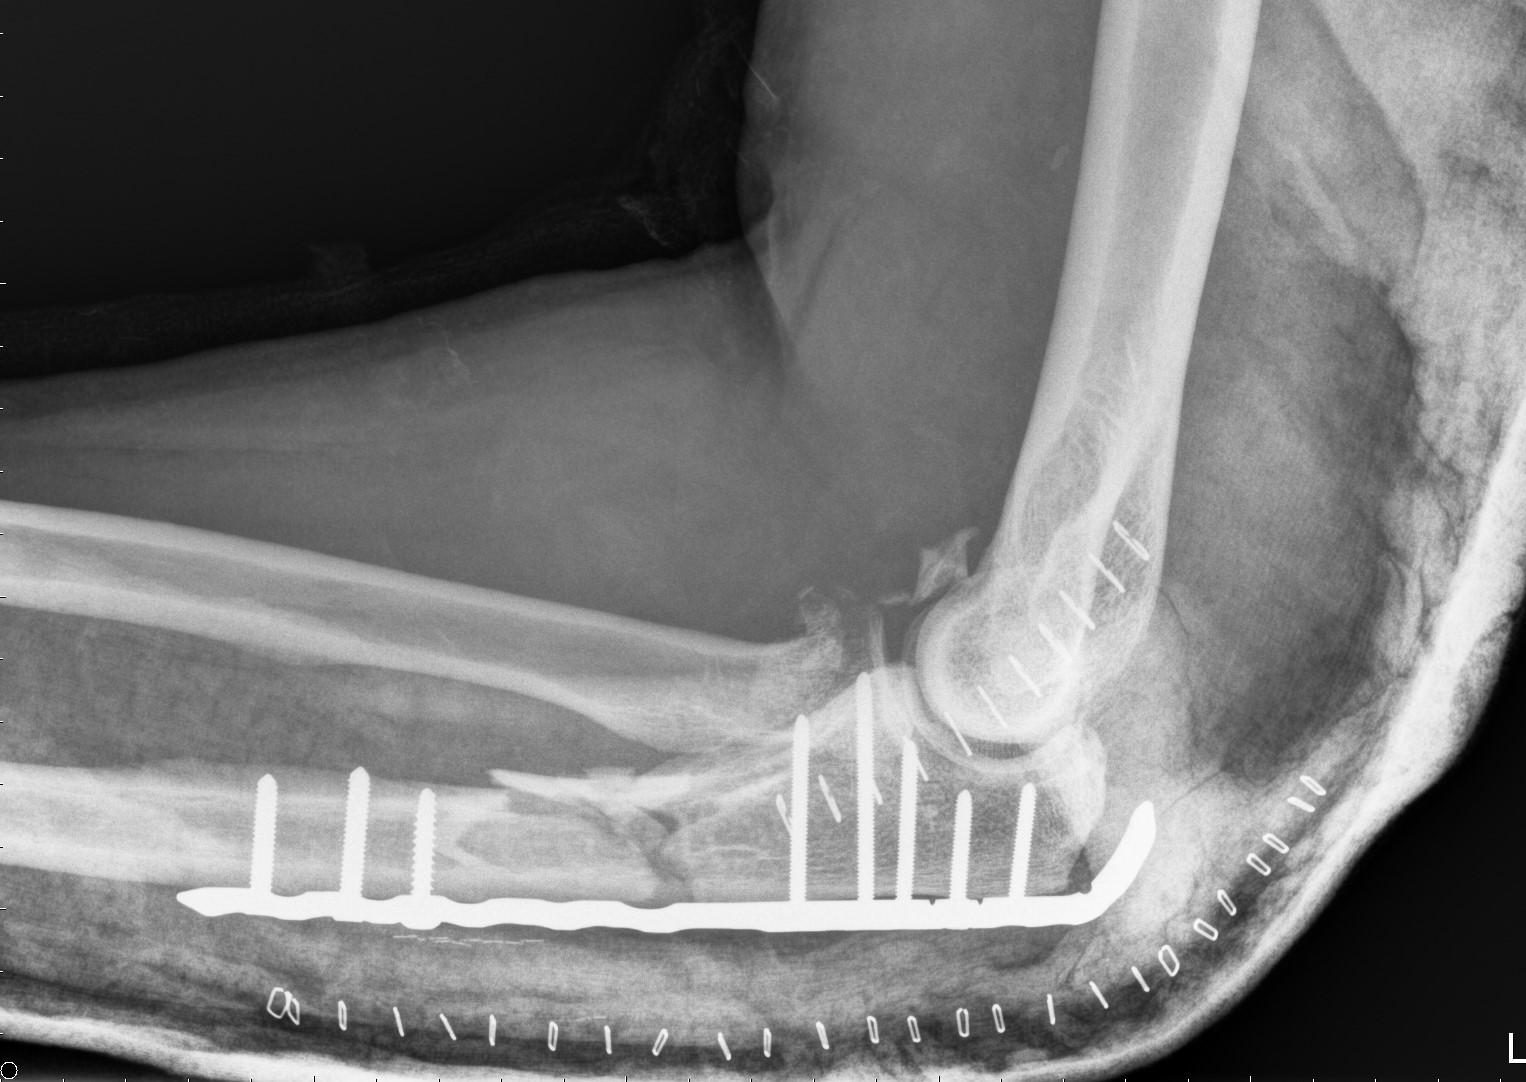

This gentleman, now in his 50's, tried to relive his youth when he jumped on his daughter's skateboard last week. A heavy fall on his left arm resulted in a fracture of the ulna you can see it in the X-ray, stabilised by a long metal plate and several screws. You can also see the two rows of metal staples closing his surgical incisions, and a few small fragments of bone around the elbow joint.

What you can't see on this post-op X-ray is the soft tissue damage. He has a combined fracture/dislocation called a 'Monteggia fracture'. The ulnar fracture is associated with dislocation of the head of the neighbouring bone, the radius. The surgeon has attempted to stabilise the radial head with a soft tissue repair, but to ensure there is no risk of re-dislocation he will be kept in a thermoplastic splint with his elbow in a bent position.